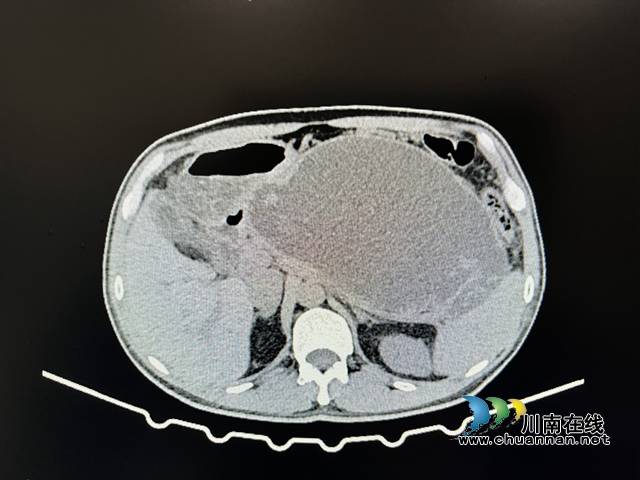

【吓人】男子突感腹痛、腹胀,竟查出西瓜大小的……

2021年起,李先生就因“急性胰腺炎”在当地医院反复住院治疗。2022年CT检查出胰腺假性囊肿(12.1*6.9cm),但因为没有症状,就决定继续观察,没放在心上。  直到一个月前,李先生出现了腹痛、腹胀症状,意识到多半胰腺又出毛病了,便...